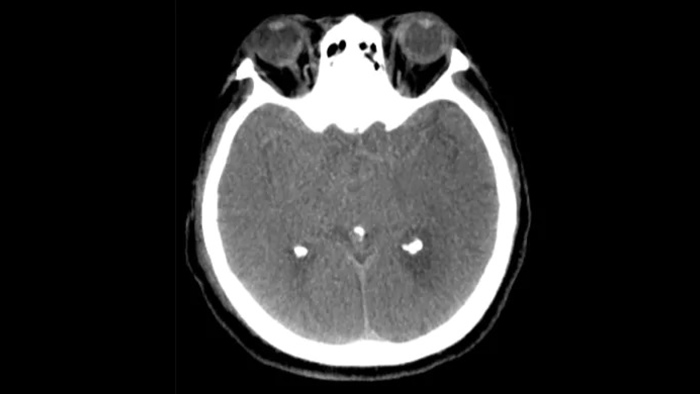

治療後の確認

SmartCT Soft Tissue

SmartCT Sofy Tissue撮影にて、出血の有無等、治療後の確認を行います。